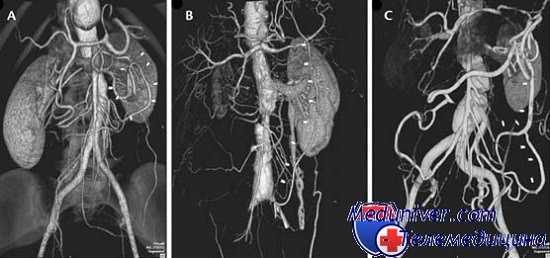

При обзорной рентгенографии брюшной полости определяется пневматизация кишечника, наличие горизонтальных уровней жидкости в брюшной полости. Специфическим методом диагностики острой окклюзии мезентериальных сосудов является селективная мезентерикография, которая уже на ранней стадии заболевания может выявить отсутствие кровотока в стволе и ветвях брыжеечной артерии. При наличии технической возможности выполняется магнитно-резонансная ангиография мезентериальных сосудов.

Реваскуляризация кишечника выполняется путем непрямой эмбол- или тромбэндартериоэктомии, в трудных случаях проводится реконструктивное обходное шунтирование с использованием сосудистых протезов (протезирование верхней брыжеечной артерии).